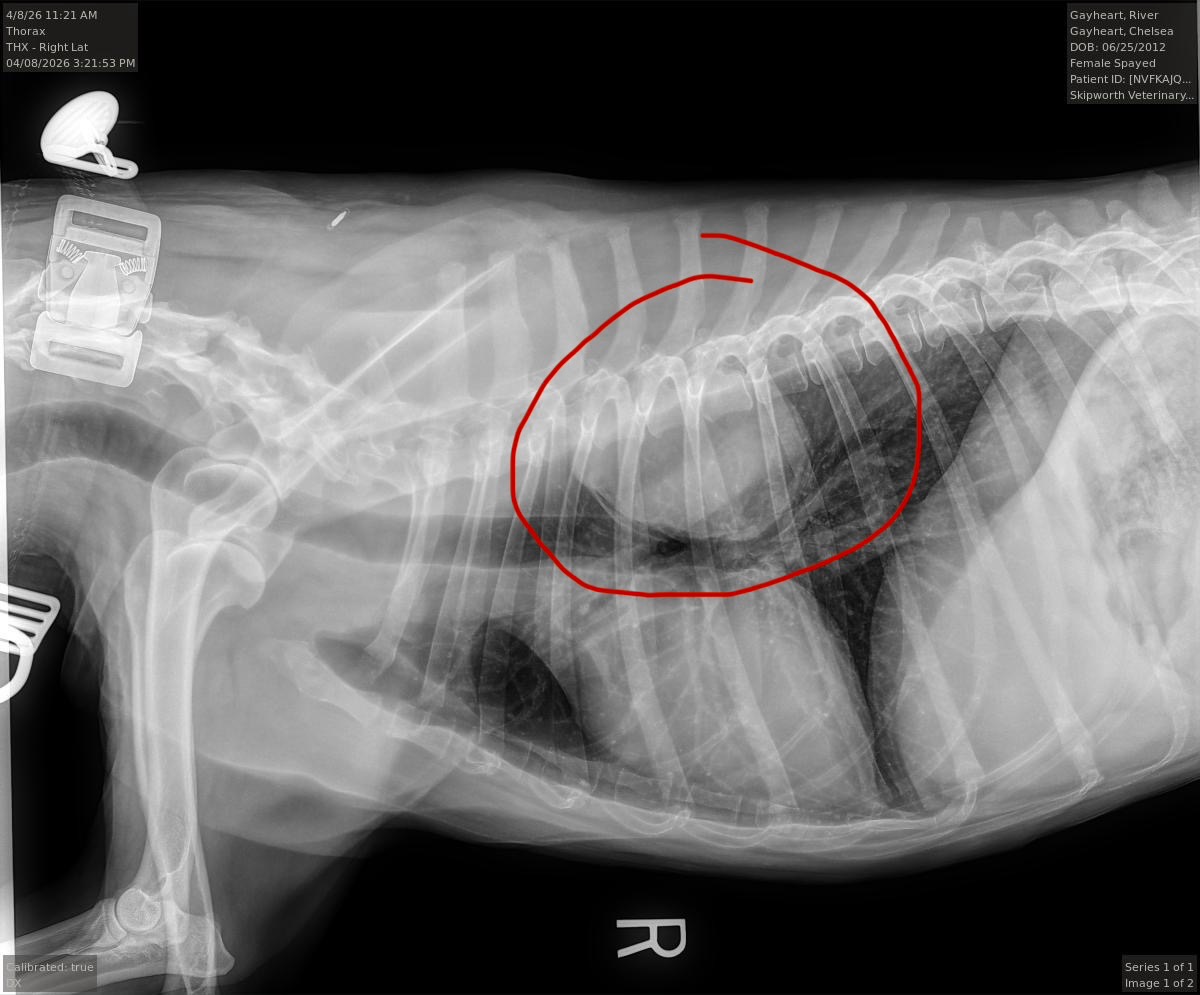

Recently, River was diagnosed with a cancerous lung tumor. Hearing that diagnosis was devastating, but we’re holding onto hope. Our veterinary surgeon has told us that surgery to remove the tumor is her best chance at more time — more walks, more tail wags, more memories.